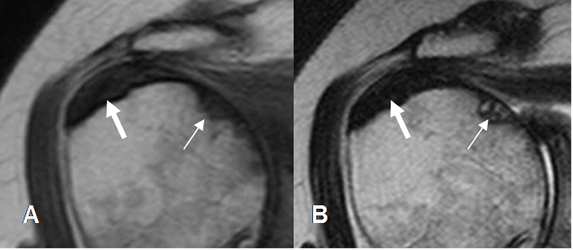

Fig 137. Tendinitis crónica reagudizada del supraespinoso.

A: RM coronal en T1 y B: RM coronal en STIR. Tendón engrosado por patología crónica. Muestra alteración de su señal, con hiperintensidad en STIR, por inflamación aguda.